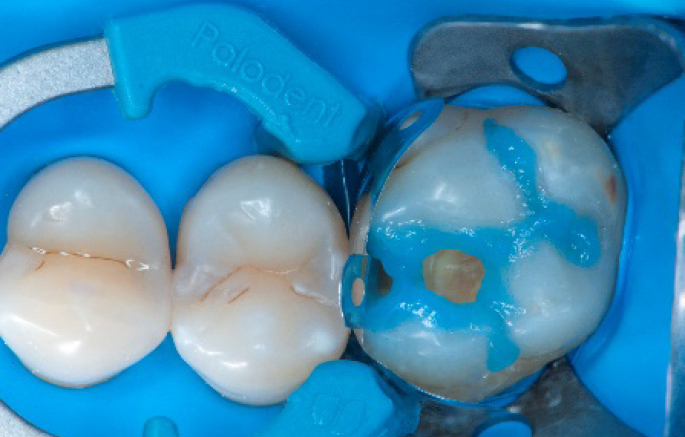

Selective enamel etching procedure with Conditioner2.

Step 7:

Adhesive application with a universal adhesive, Prime&Bond3.

Step 8:

Transformation of class II into class I, restoring the interproximal wall with Spectra ST4 composite in shade A2.